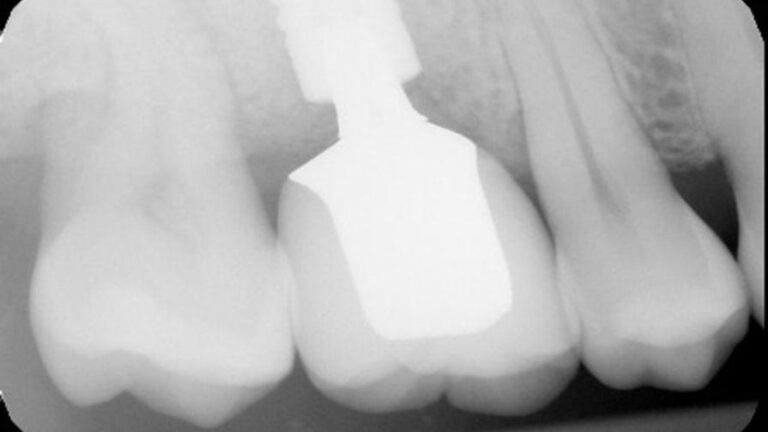

This case involves a fractured Atlantis zirconia abutment in an Ankylos 4.5 implant in the #3 site.